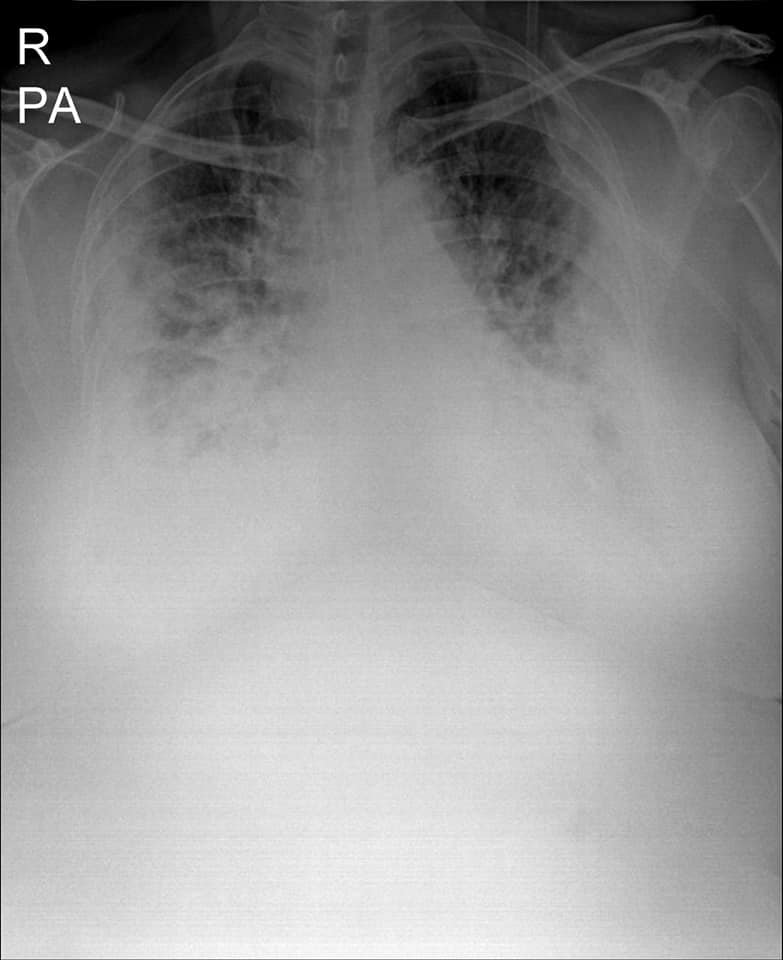

“មានបទពិសោធន៍ជាង1ឆ្នាំក្នុងគ្រប់គ្រង និងព្យាបាលជំងឺកូវីដដោយគ្មានការភ័យខ្លាចឬតក់ស្លុតឡើយ ។ តែក្នុង1ខែចុងក្រោយនេះចាប់ពី 20 កុម្ភៈ 2021 ខ្ញុំមានអារម្មណ៍ភ័យខ្លាច និងព្រួយបារម្ភណាស់ ពីព្រោះវាជាប្រភេទមេរោគប្រែរូបថ្មី (variant virus strain) ដែលក្នុងរយៈពេលតែ2ទៅ5ថ្ងៃវាវាយលុកចូលសួតធ្វើអោយរលាកធ្ងន់ធ្ងរទាំងសងខាង ។ រូបភាពសួតត្រូវបានមេរោគស៊ីសុះសាច់ដ៏គួអោយខ្លាច ។